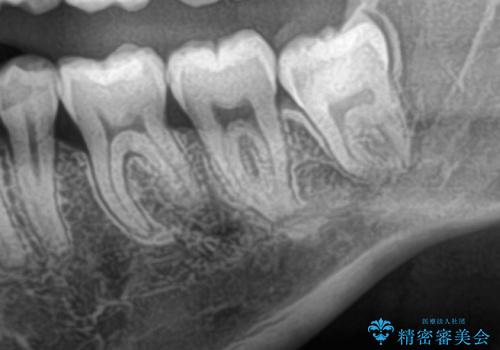

- 親知らずを抜きたいとのことで来院された患者様です。

CTで神経の位置などを確認し、抜歯術を行いました。